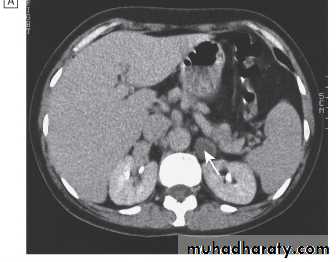

Localisation; abdominal CT or MRI.

CT scan of abdomen showing large left adrenal phaeochromocytoma. The normal right adrenal (white arrow) contrasts with the large heterogeneous phaeochromocytoma arising from the left adrenal gland (black arrows).